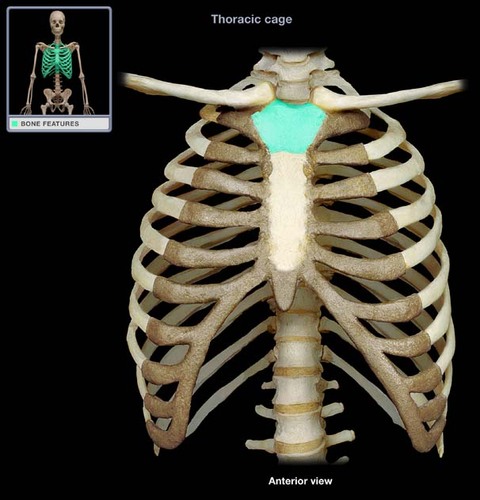

sterum

29

New cards

Sternum body

30

New cards

sternum manubrium

31

New cards

sternum xiphoid process